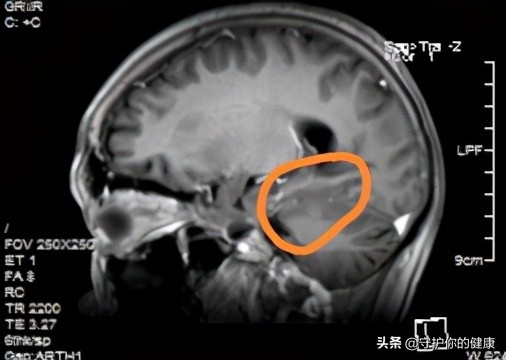

这是靶向治疗后:

吃药后

两图对比肿瘤是明显缩小的。